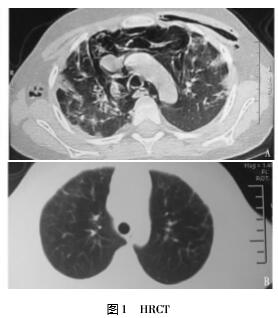

典型病例患者,男性,5岁,因反复发热、乏力、面部皮疹5月余,右颈部痛26d、左胸痛22d入院。外院考虑“皮肌炎”口服激素治疗3月余。查体:T37.8℃,P110次/min,R28次/min,面部散在紫红斑,Gottron征(+),指端血管炎表现(+);右侧颈部、右侧上肢及左侧胸壁、上腹壁可触及散在皮下握雪感;双肺呼吸音低,可闻及细小湿啰音,四肢近端肌力Ⅲ+。辅助检查:肌酶CK58U/L,LDH553U/L,HBDH390U/L,HRCT示:双肺弥漫间质性改变、合并感染;纵膈、左胸壁、右腋下皮下气肿,见图1A。肌电图示:肌源性损伤;痰培养:铜绿假单孢菌,酵母型真菌菌落;多次检查G试验阳性。血气分析示:低氧血症。诊断:皮肌炎合并纵膈、皮下气肿,肺部混合感染。予MP40mg/d×7d,渐规律减量,IVIG10g/d×5d,同时予舒普深、伏立康唑、复方新诺明等抗感染,感染控制后加服K5061mg/d,至病情缓解稳定。住院152d,皮疹消退、肌力恢复正常,纵膈、皮下气肿完全吸收,双肺轻度间质改变。1年后双肺间质性病变亦明显改善,见图1B。